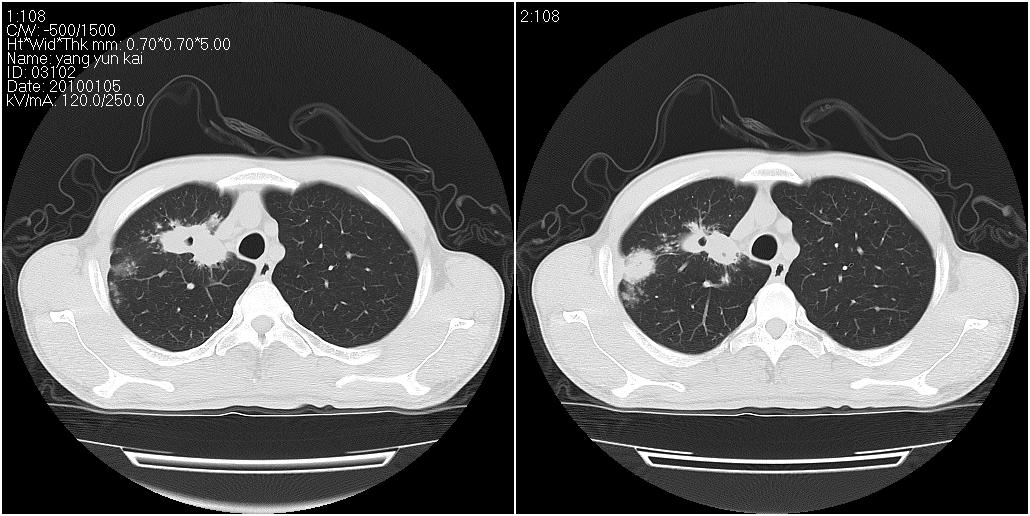

标题: CT23980:男性,47岁。近来咳痰、咳血,血沉增快(40左右),

男性,47岁。近来咳痰、咳血,血沉增快(40左右),痰中未检出结核杆菌。

两肺继发性肺结核并多发性结核球形成,部分病灶内空洞形成。